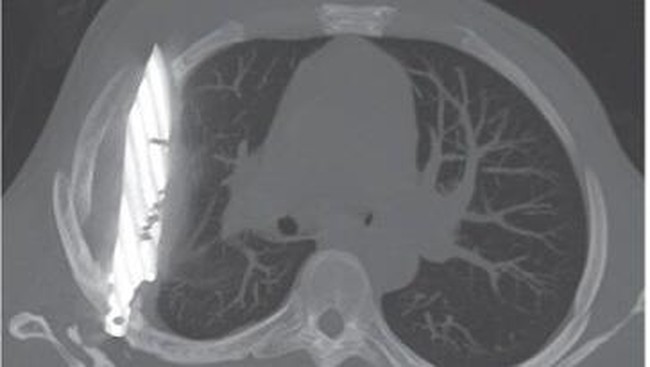

Penampakan pisau menancap di dada pasien pria. (Foto: Journal of Surgical Case Reports)

"Rontgen dada lateral awal menunjukkan adanya benda logam tersangkut di bagian tengah dada, dengan bayangan samar di sekitarnya yang mengindikasikan hematoma terlokalisasi kronis yang mengeluarkan cairan, atau fibrosis pascatrauma, kemungkinan besar akibat luka tusukan pisau pasien," tulis dokter dalam jurnal, dikutip dari News18, Selasa (19/8/2025).